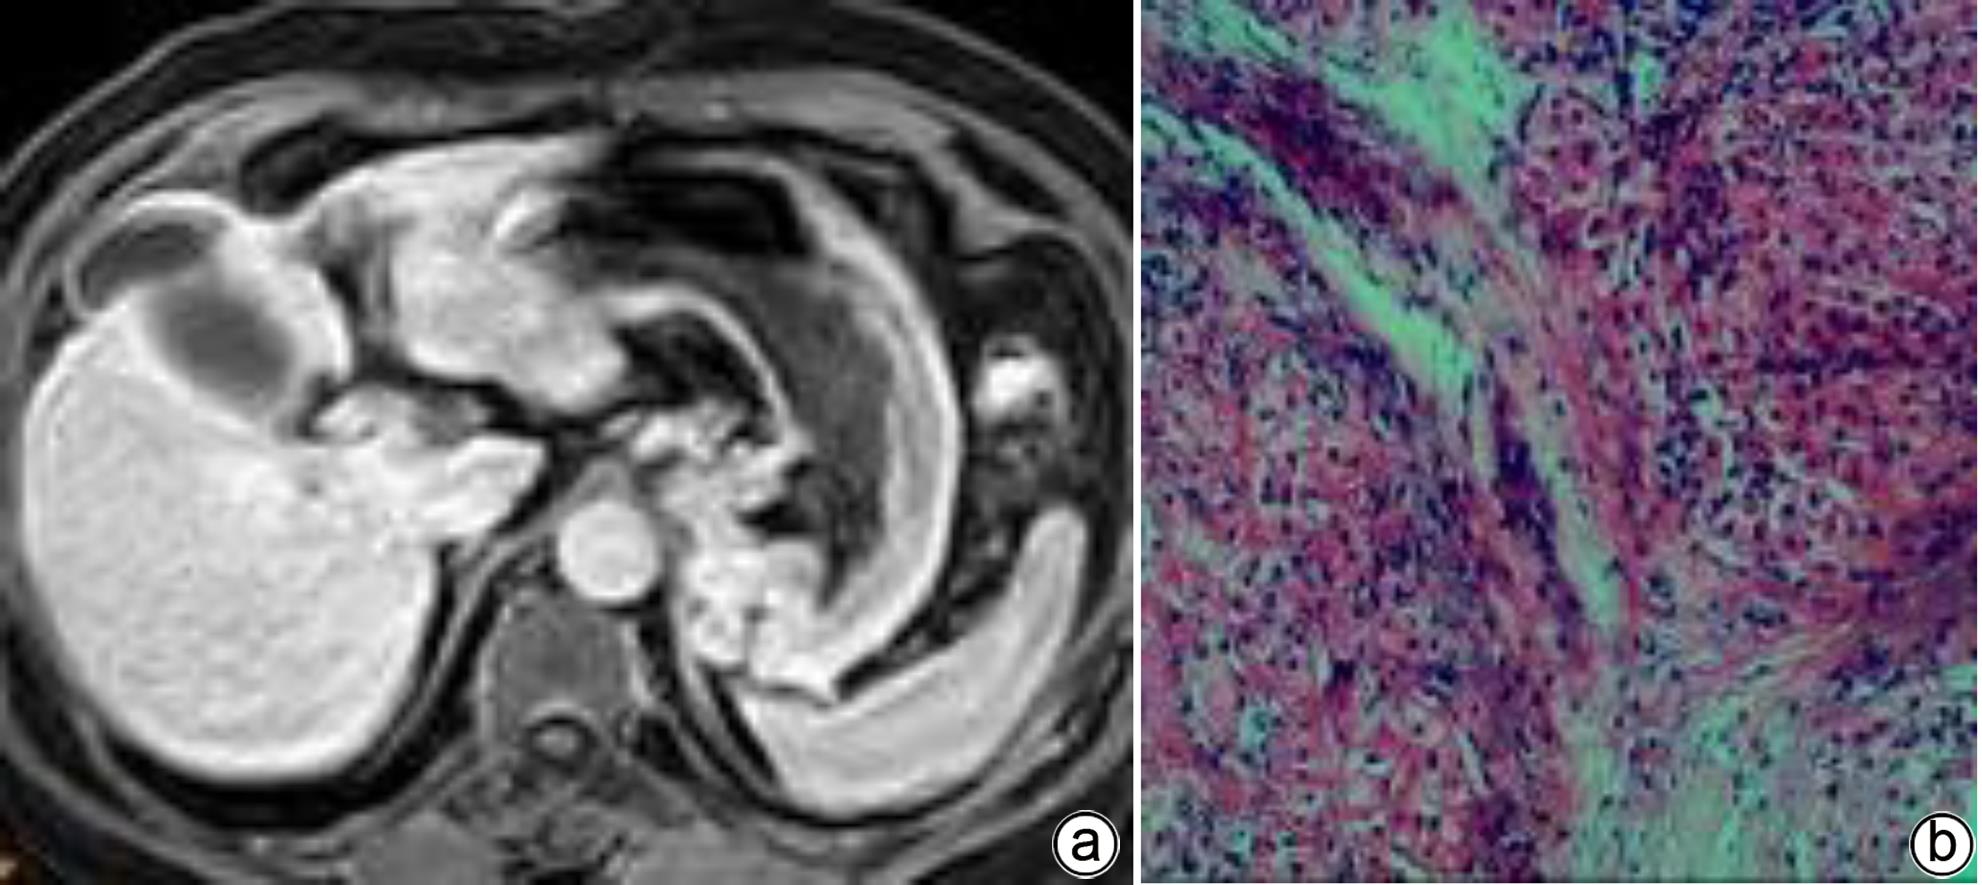

Value of MRI biliary score and liver/muscle ratio in evaluating the pathological grade of liver fibrosis

Lu HUANG, Lijian LU

2024, 40(4): 720-725. DOI: 10.12449/JCH240413

Abstract(1187) HTML (328) PDF (1168KB)(71)

Abstract:

Objective  To investigate the value of biliary score and hepatic signal intensity-to-muscle signal intensity ratio (HMR) obtained by multiphase contrast-enhanced MRI scan using Gd-EOB-DTPA in evaluating the pathological grade of liver fibrosis.  Methods  A retrospective analysis was performed for the MRI and clinical data of 51 patients with chronic hepatitis B liver fibrosis in Wuming Hospital Affiliated to Guangxi Medical University from January 2020 to May 2023. The 51 patients with liver fibrosis were divided into low-grade group (S1-S2) and high-grade group (S3-S4). GE Architact 3.0T MR scanner was used to perform MRI scans, including routine plain scan and contrast-enhanced scan at arterial phase, portal venous phase, delayed phase, hepatobiliary phase, and excretory phase, and biliary score and HMR were measured for the patients with different grades of liver fibrosis. The t-test was used for comparison of continuous data between groups, and the chi-square test or the Fisher’s exact test was used for comparison of categorical data between groups. The receiver operating characteristic (ROC) curve was plotted to evaluate the value of MRI indicators in determining the pathological grade of liver fibrosis.  Results  Among the 51 patients with liver fibrosis, there were 30 patients in the low-grade group and 21 in the high-grade group. Compared with the high-grade group, the low-grade group had significantly higher biliary score (3.67±0.55 vs 2.57±0.75, t=6.05, P<0.001) and HMR at portal venous phase (2.38±0.76 vs 1.97±0.18, t=2.41, P=0.020), delayed phase (2.48±0.70 vs 1.99±0.27, t=3.09, P=0.003), and hepatobiliary phase (4.10±0.63 vs 3.16±0.47, t=5.81, P<0.001). The above indicators had an area under the ROC curve (AUC) of 0.86, 0.79, 0.82, and 0.88, respectively, in distinguishing low- and high-grade liver fibrosis, with a positive rate of 70%, 63.3%, 83.3%, and 96.7%, respectively, and a negative rate of 90%, 95.2%, 74.1%, and 100%, respectively, in the diagnosis of high-grade liver fibrosis. Biliary score combined HMR had an AUC of 0.95, with a positive rate of 85.7% and a negative rate of 96.7%.  Conclusion  Biliary score and HMR at hepatobiliary phase obtained by multiphase contrast-enhanced MRI scan using Gd-EOB-DTPA has a relatively high diagnostic efficacy in distinguishing between low- and high-grade liver fibrosis and a certain guiding value for the diagnosis and treatment of liver fibrosis in clinical practice.